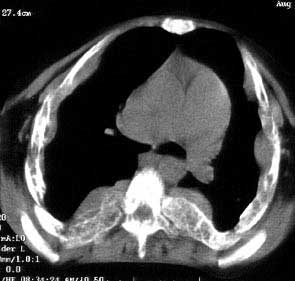

以下是引用jiajie在2004-12-10 22:14:53的发言:[br]多发性肋骨骨质疏松,[br][br]麦粒状及筛孔状骨质破坏,[br][br]髓腔膨胀皮质变薄,[br][br]骨旁多发软组织肿块,[br][br]考虑恶性病变,支持肋骨多发性骨髓瘤。

以下是引用pujunzhi在2008-7-3 21:21:00的发言:[br]支持地中海贫血伴髓外造血可能性大,需与多发性骨髓瘤、淋巴瘤等鉴别。